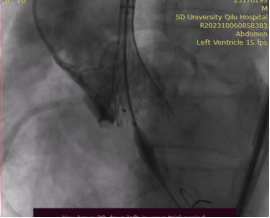

患者老年男性,因“发作性晕厥1年,加重10余天”就诊。患者入院后经药物治疗,仍反复发作胸闷胸痛,症状难以控制。心血管内科主任张澄教授立即组织病例讨论,制定治疗策略,评估相关手术风险及预后。考虑患者主动脉瓣重度狭窄,瓣口面积仅有0.36cm2,跨瓣压差高达128mmHg,经充分讨论并与家属反复沟通后,决定对该患者实施经导管主动脉瓣置换术(TAVR)。手术团队由心血管内科安贵鹏、孟晓、董梅、刘祥娟、马连越和曹媛组成,心血管内科主任张澄进行全程指导。手术采用了最新的极简式TAVR,应用局部麻醉和加硬导丝起搏,不再进行全麻、镇静、食道超声指引或置入尿管。术中造影见主动脉瓣重度钙化,结合术前分析,选用了20mm球囊行预扩张,高位释放26mm的VenusA-Valve瓣膜。释放完成后重复造影可见人工瓣膜位置准确,形态良好,未见主动脉瓣反流及瓣周漏,跨瓣压差由术前120 mmHg,降至2mmhg,手术成功。